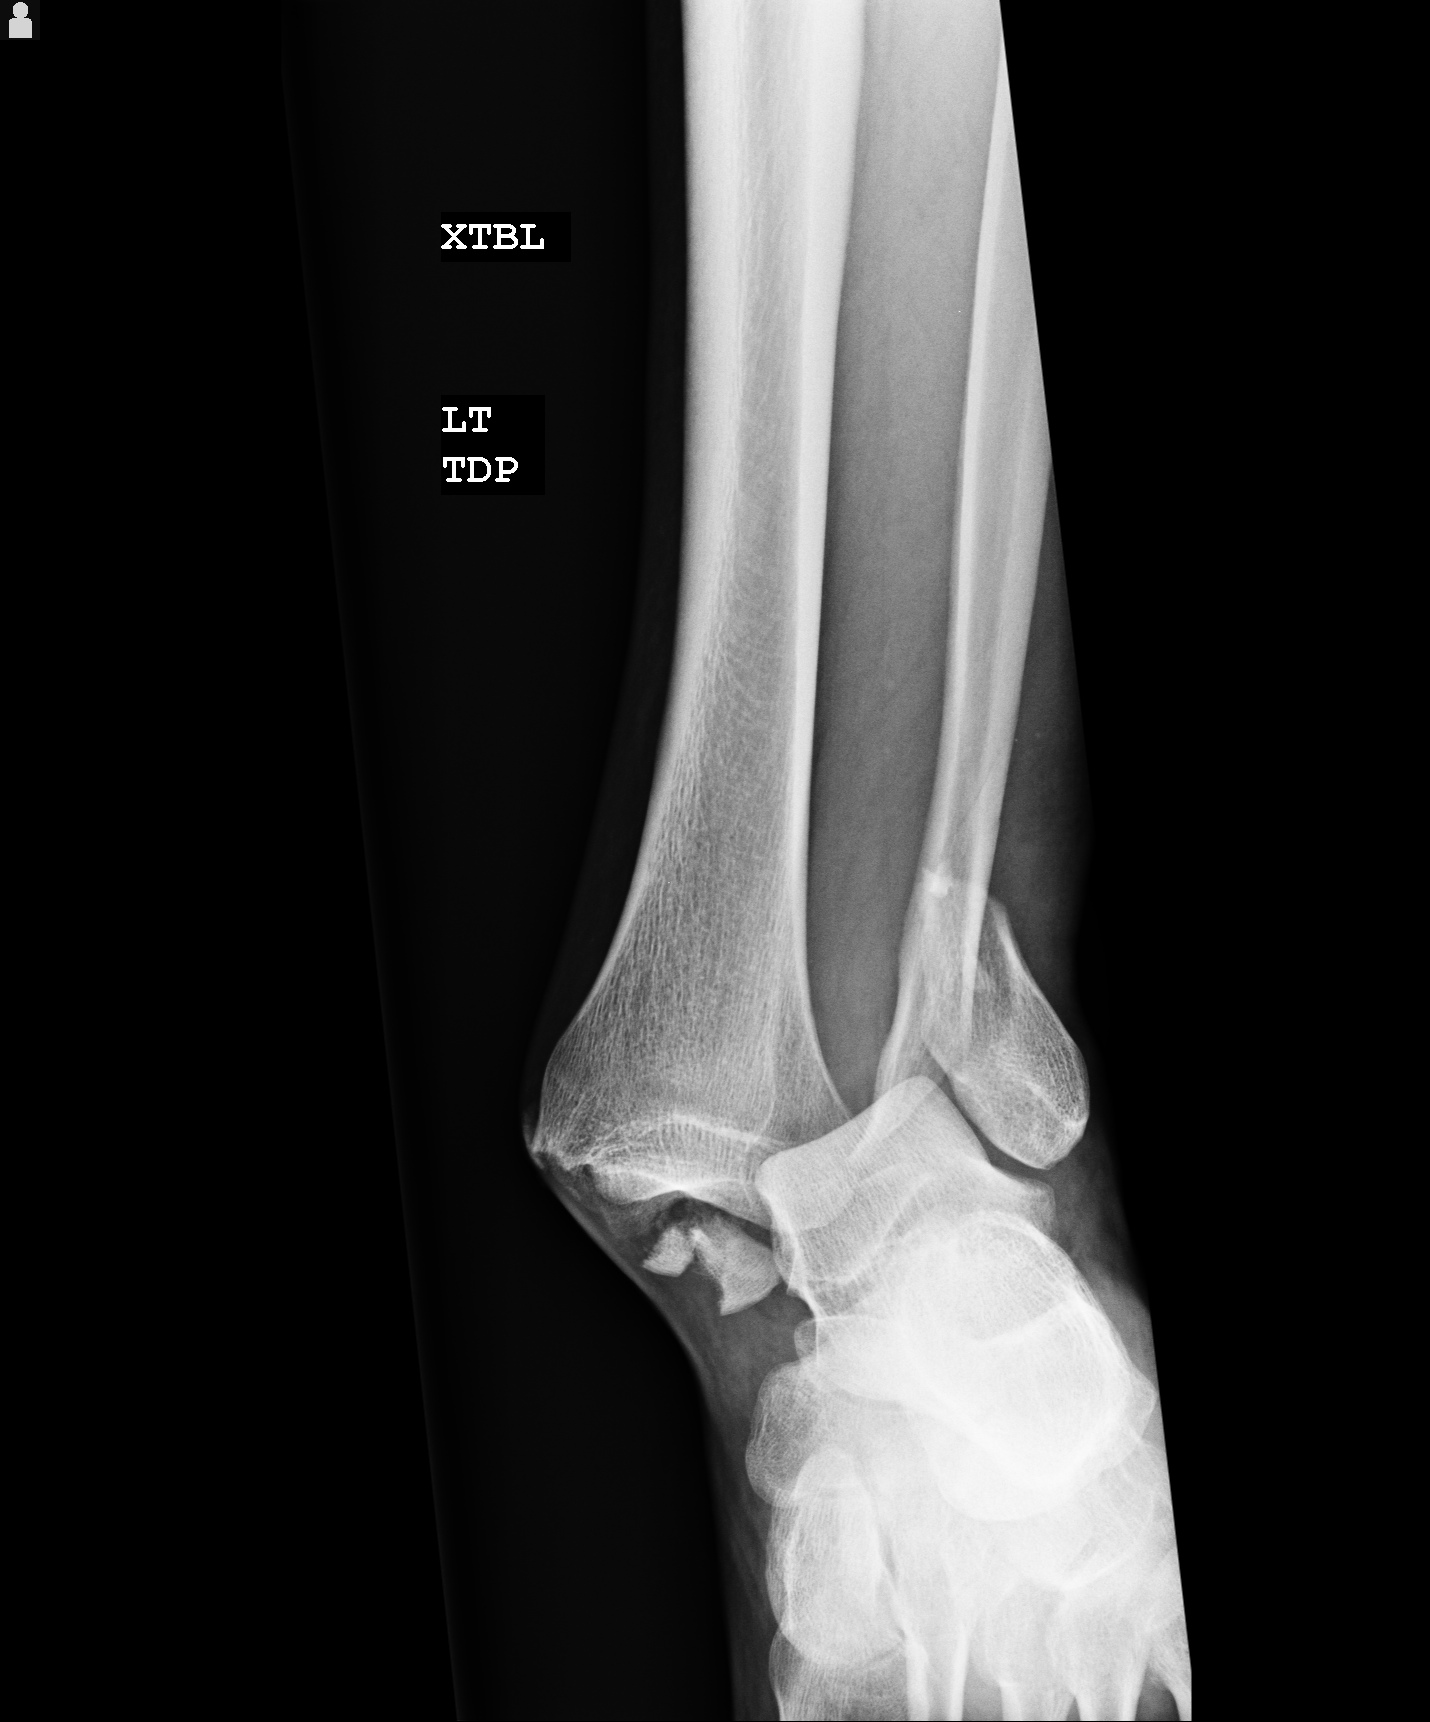

Partially dislocated fibula. Legs of a child showing a partial dislocation (subluxation) of the Why Does My Leg Keep Dislocating They can affect any joint in. Your knee contains four bones—the thigh. a dislocated knee occurs when the bones that form your knee are out of place. — a dislocated kneecap is a common injury when a person changes direction suddenly with their feet planted. — a knee dislocation is an uncommon but extremely serious injury in. Why Does My Leg Keep Dislocating.